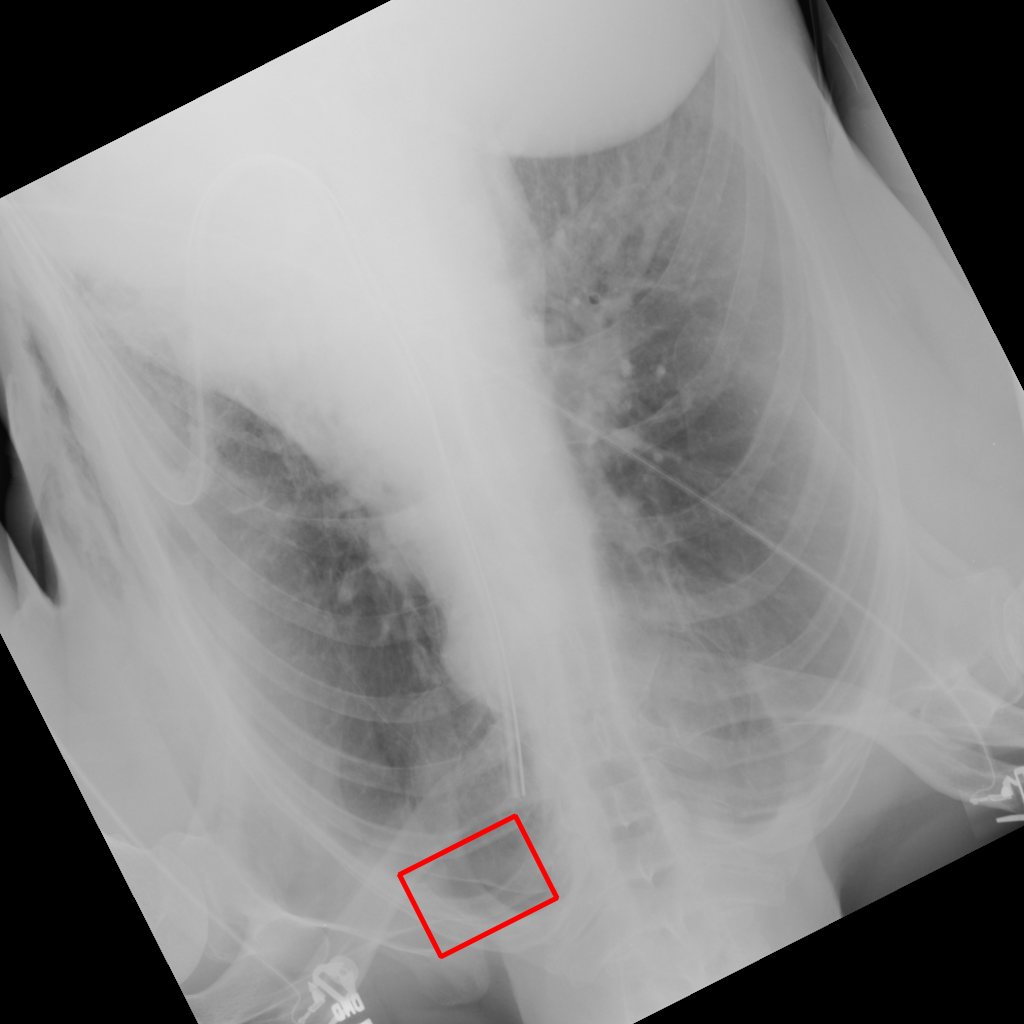

X-ray Motion Blur

X-ray GMAIMMbench Disease Diagnosis

X-ray Motion Blur - L0 (Original)

L0

L0 (Original)

X-ray Motion Blur - L1 (Moderate)

L1

L1 (Moderate)

X-ray Motion Blur - L2 (Severe)

L2

L2 (Severe)

Question

Considering the box-marked region in the X-ray image, what is the most likely diagnosis?

A cardiomegaly B pneumothorax C pulmonary nodule D pleural thickening

Ground Truth: B. pneumothorax